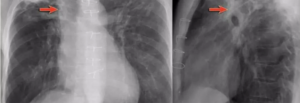

shows a right upper lobe airspace opacity adjacent to the trachea.

• ⁠ ⁠focal or patchy heterogeneous consolidation involving the apicoposterior segments of the upper lobes and the superior segments of the lower lobes

lateral view of the same patient, the typical location of the apicoposterior segment